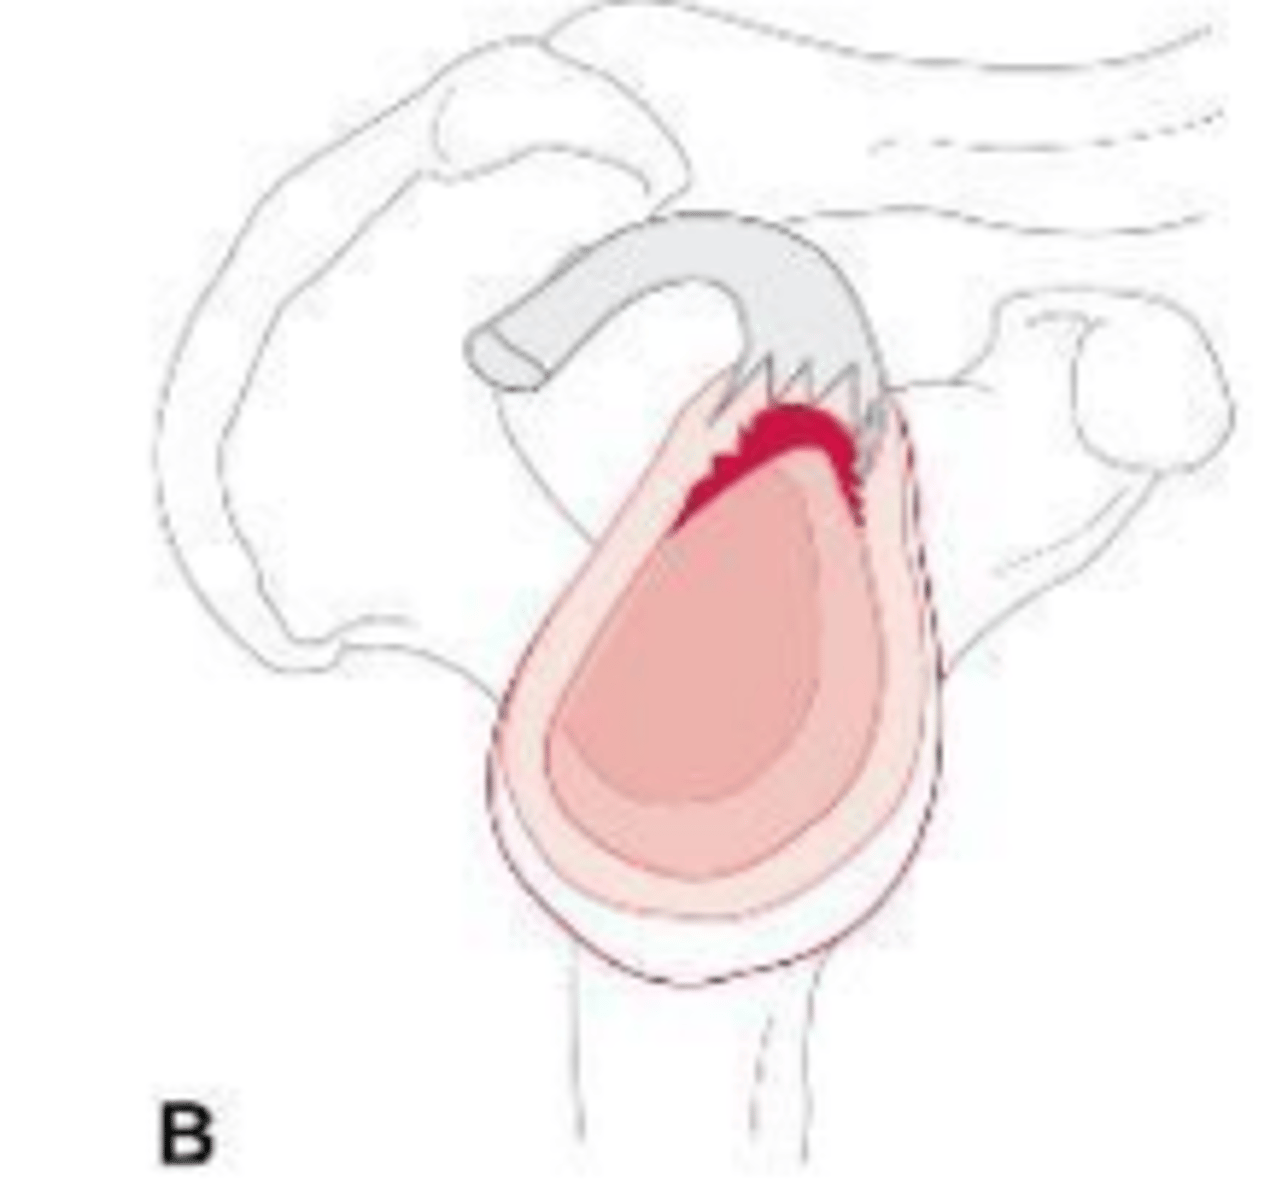

What does the image show?

Worn tissue of biceps tendon and labrum

What does the image show?

Biceps tendon and labrum becoming detached